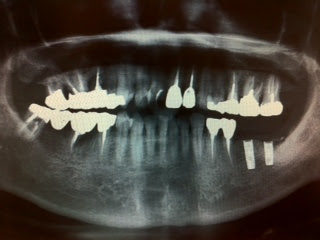

今週のオペは左下6・7部位にアストラインプラント直径4.0 8㎜ 直径3.5 8㎜を合計2本埋入しました。

去年の12月に左下7は抜歯していて、その時にテルプラグをいれました。

左下6番部は骨幅がなく、CGF+人工骨でGBRしました。

右上前歯は今年2月にオペして、8月にセラミックをセットして入れ歯から解放されてとても喜んでいらっしゃいます。